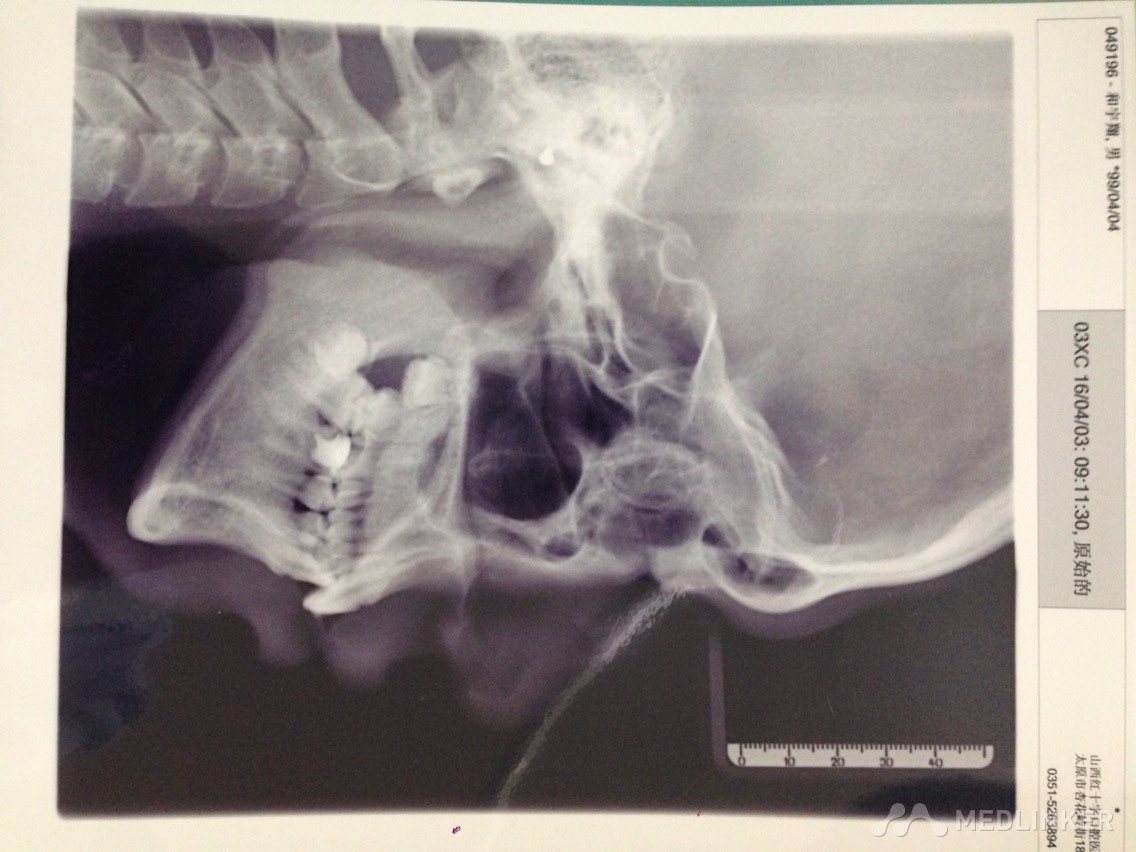

患者男,17岁,上前牙不美观要求矫正

各位同仁帮忙看下这个患者适合怎么矫正?

各位同仁帮忙矫正的方案是怎么样?